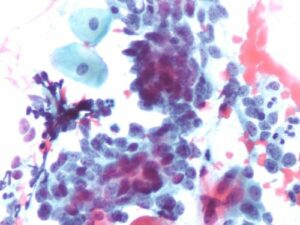

Identificades vulnerabilitats clau del càncer mitjançant anàlisi Big Data

Un mateix tumor, o inclús una mateixa cèl·lula tumoral, pot presentar múltiples alteracions del genoma [...]